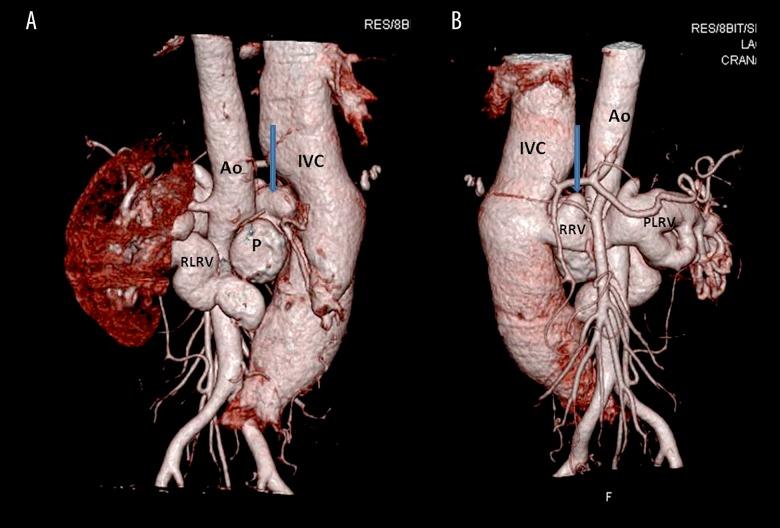

A 29-year-old male presented to the cardiology department with complaints of breathlessness, abdominal pain and hematuria for the last 6 months. On clinical examination there was evidence of audible bruit over the abdomen. He had a past history of a gunshot injury around two years back. CT angiography revealed a large partially calcified pseudoaneurysm arising from the right lateral wall of the abdominal aorta with the neck of the pseudoaneurysm at juxtarenal location with a fistula between the anterior wall of the pseudoaneurysm and the posterior wall of the right renal vein. There was an associated incidental finding of circumaortic left renal vein with gross aneurysmal dilatation of both pre- and retro-aortic part of the renal vein.

Delayed presentation of aortic pseudoaneurysm with its fistulous communication with the right renal vein is a rare entity. CT angiography is a non-invasive modality for diagnosis of the exact site of communication, length of aneurysm, proximal and distal extent of the affected segment and its relationship with surrounding structures.